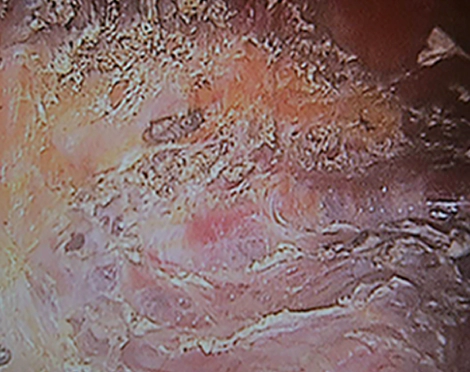

MINE dry pocket breast surgery

Endoscopic view of a dry pocket made during Korean breast augmentation.